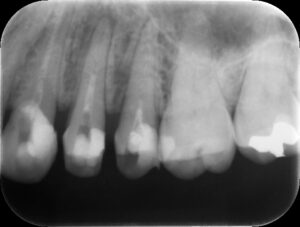

根管充填後レントゲン。歯の痛みや歯茎の腫れが改善したため、バイオセラミックシーラーおよびガッタパーチャにて根管充填を行った。根管治療は2回、2週間で終了。